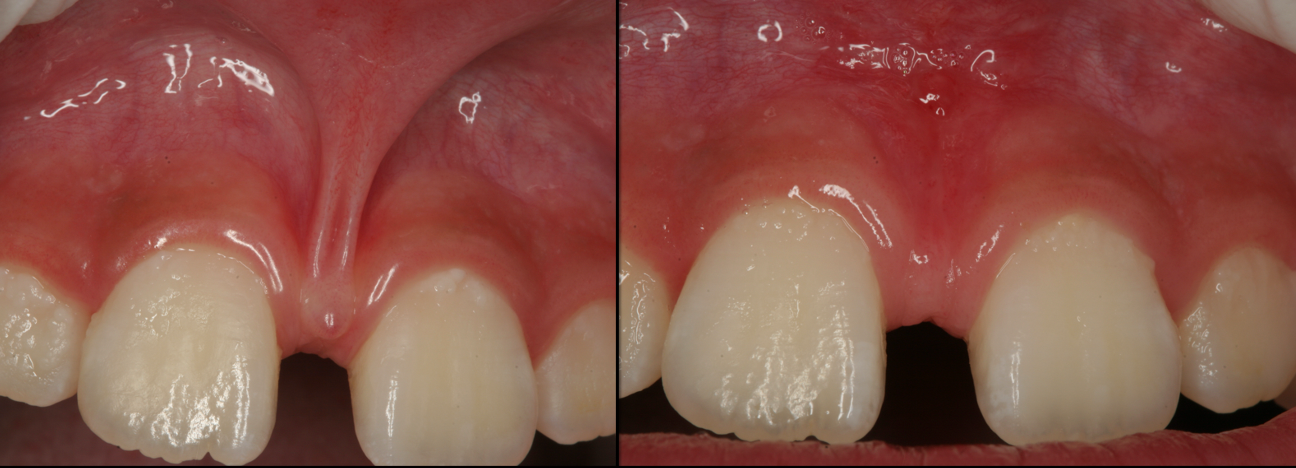

Manage small and large frenum pulls.